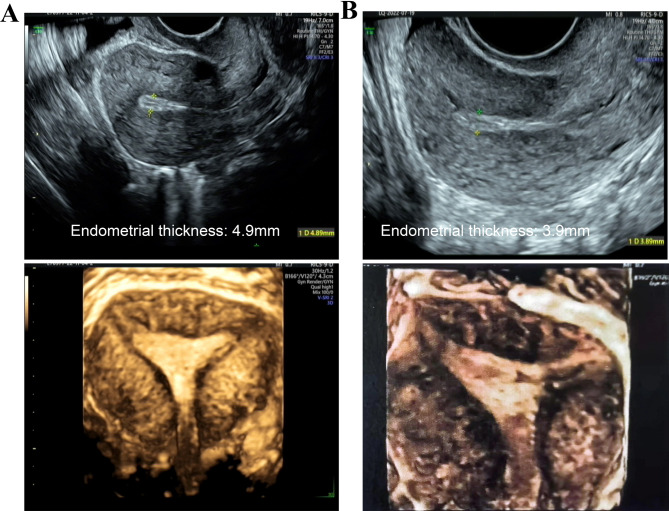

Case presentation: We report the case of a 29-year-old woman with severe IUA, RSA, and PCOS, who experienced three spontaneous abortions. Copy number variations (CNV's) detection of fetal villi from the last abortion indicated Turner syndrome. Hysteroscopic adhesiolysis (HA) had been performed twice previously. She subsequently underwent superovulation using an antagonist regimen, resulting in oocyte retrieval and cryopreservation of four transplantable blastocysts after genetic testing. After three rounds of HA, the uterine cavity shape returned to normal. She then received two cycles of Femoston and/or estradiol valerate therapy combined with oral low-dose aspirin, vaginal sildenafil, pelvic floor electrical stimulation, and uterine perfusion platelet-rich plasma (PRP); however, the frozen embryo transfer (FET) was canceled as the EMT remained 4.9 mm and 3.9 mm. After three additional HA procedures and one hysteroscopy, the uterine cavity returned to normal. She then received tamoxifen (TAM) with estradiol valerate and human menopausal gonadotropin (HMG), achieving an EMT of 7.5 mm after ovulation. Ultimately, the frozen transfer of a 4BB blastocyst resulted in the birth of a healthy baby boy.